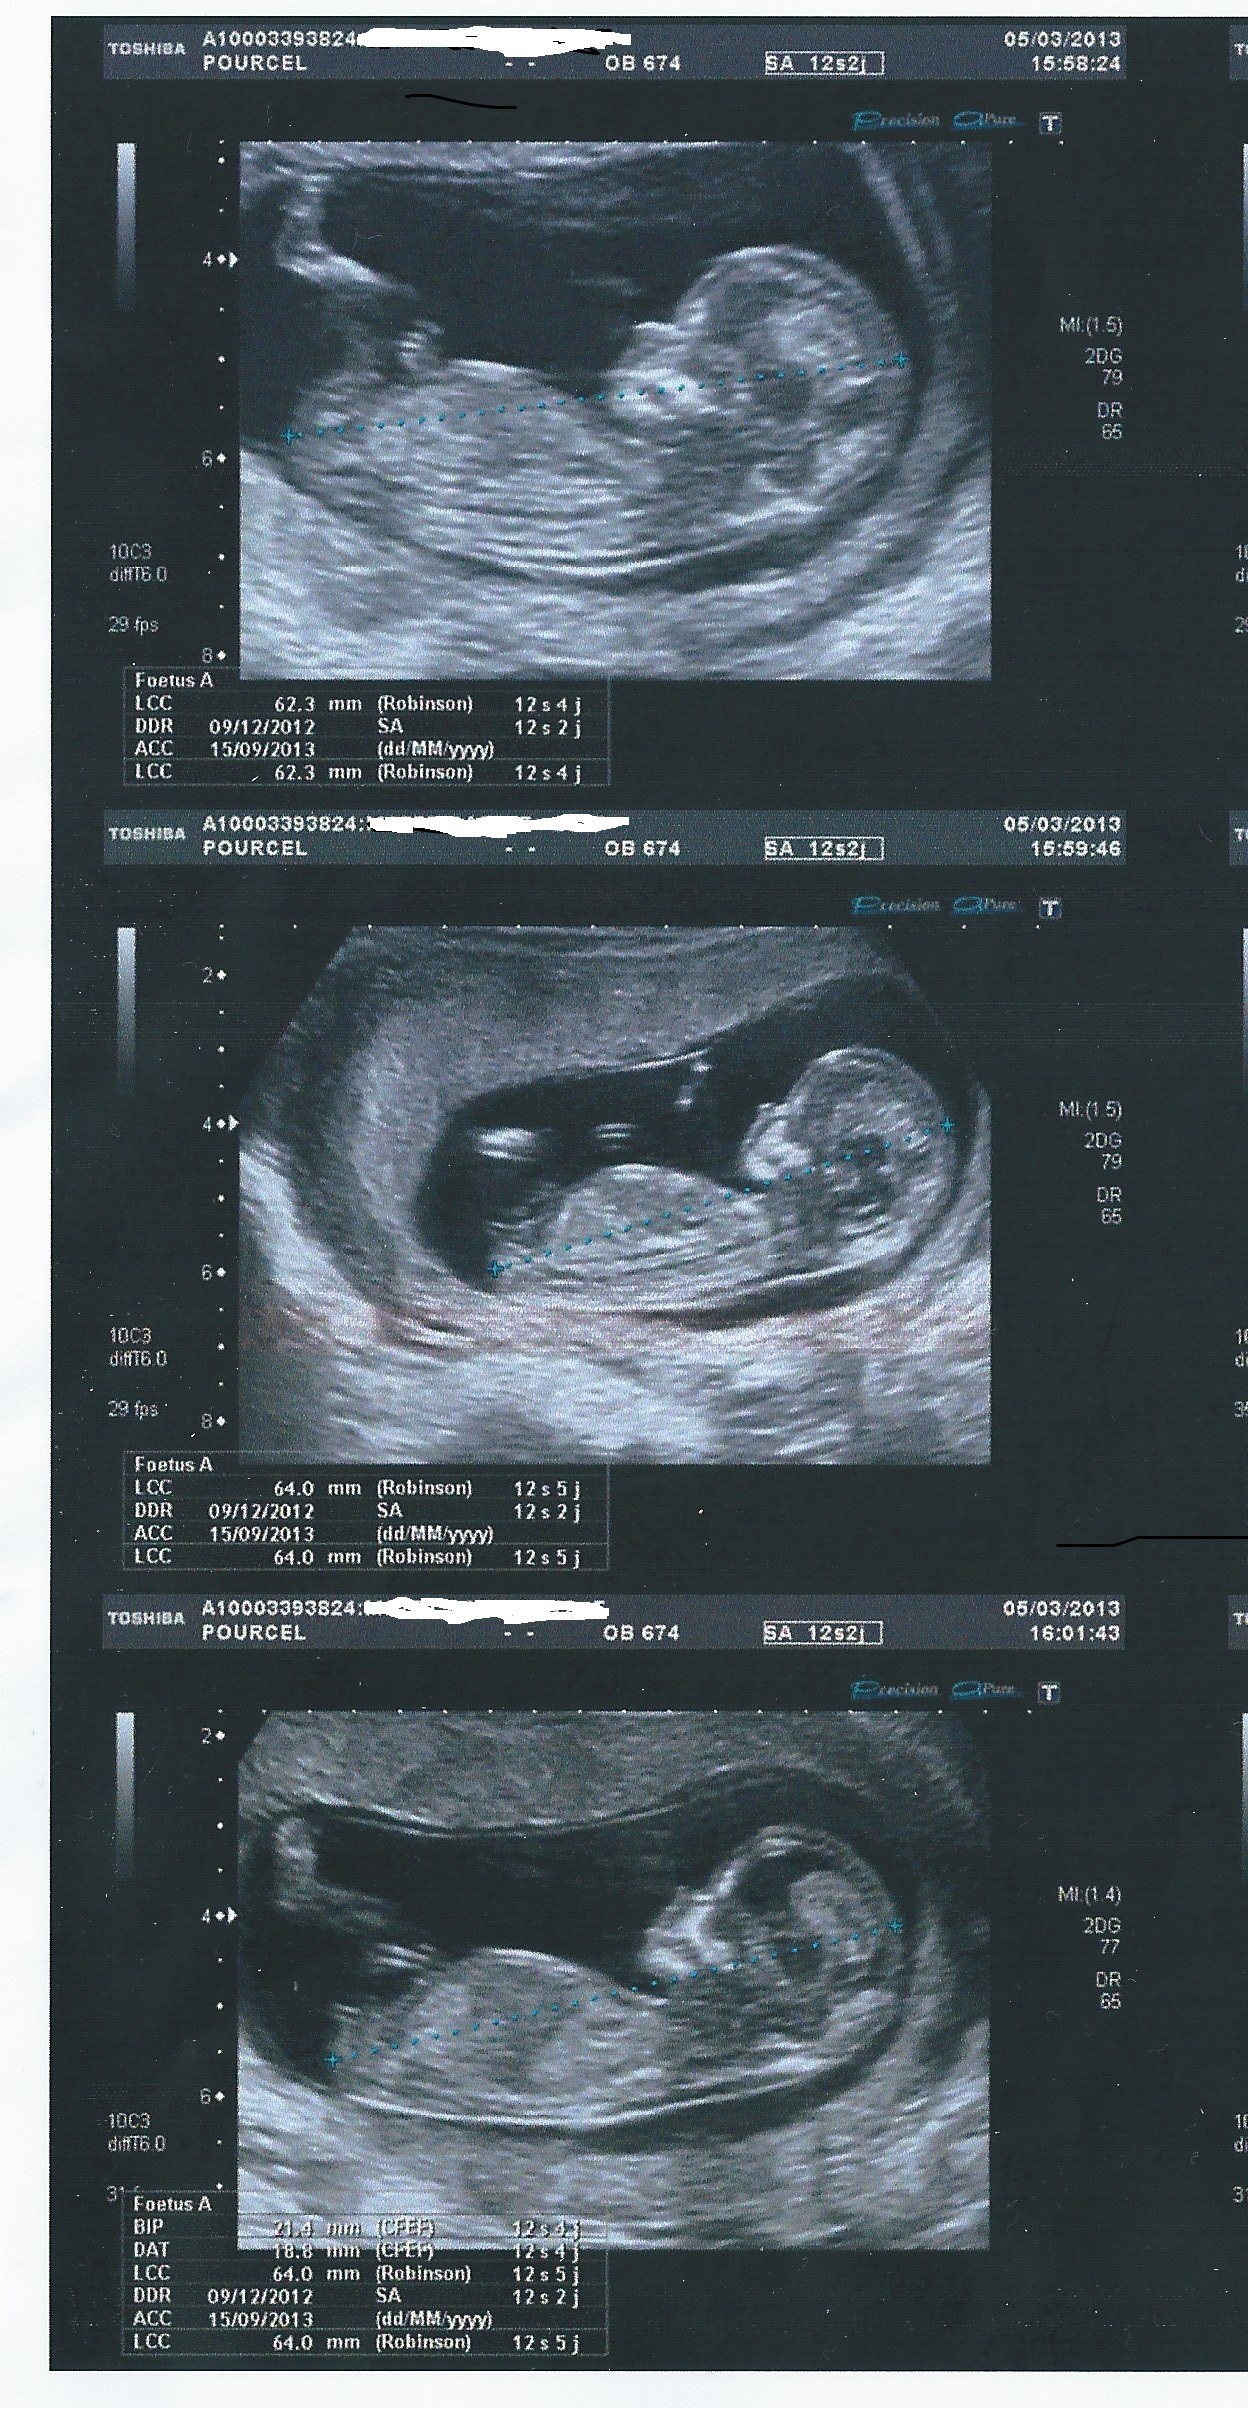

A partir de la 14e ou 15e semaine de grossesse, le ou la gynécologue est en mesure de reconnaître distinctement le sexe du bébé à l'aide d'une échographie Les organes génitaux seront alors visibles sur l'écranQue des histoires de grandsmères et des mythes étranges, mais de quoi passer le temps avant le grand jour!Actuellement il ne faut pas déterminer le sexe fœtal à partir du tubercule génital avant 12 SA car le taux d'erreur est de 40 % et donc ne dépasse que de peu l'effet du hasard l'aspect est dit féminin quand le le tubercule génital part vers le bas et horizontalement l'aspect est dit masculin quand le tubercule génital part en avant et

Ce test peut être demandé quand il y a un risque de certaines maladies génétiques touchant un sexe ou l'autre", précise le gynécologue Quand savoir le sexe de son bébé ?Selon la « nub theory » ou méthode du bourgeon génital, on peut, dès 12 semaines d'aménorrhée environ, avoir une idée du sexe de bébé en étudiant l'angle entre le bourgeon et la colonne vertébrale Chez un garçon, le bourgeon forme un angle d'approximativement 30 degrés avec la colonne vertébraleLe 05h52 Lecture en 3 min L'annonce du sexe du bébé se fait lors de la seconde échographie, entre la e et la 22e semaine de grossesse Mais tout dépend de la façon dont les organes génitaux se développent et du bon vouloir de bébé qui accepte, ou non, ce jourlà de dévoiler son sexe Sexe de bébé rien de

Il y a à peine quelques années, l'échographie était le seul procédé offert aux femmes enceintes afin de connaitre le sexe de l'enfant qu'elles portaient Ainsi, la majorité des futures mères attendaient jusqu'à la moitié de leur grossesse pour réaliser une échographie qui confirmerait le sexe du bébéIl est possible d'avoir une indication sur le sexe de votre enfant lors de votre échographie du premier trimestre en observant l'aspect du tubercule génital du fœtus Cette méthode, dite du bourgeon génital donne de bons résultats, en particulier pour les échographies réalisées à partir de 11 semaines de grossesse (13 semaines dCette façon de faire estelle fiable ?

Et comme tout parent, l'envie de savoir s'il s'agit d'une fille ou d'un garçon Mais estce que le gynécologue estil déjà dans la capacité de dire le sexe de bébé ?C'est possible On peut déjà se faire une petite idée du sexe à l' échographie des 12 semaines Au cours de cet examen, le médecin scrute les différents organes, notamment le tubercule génital Un certain nombre de travaux ont démontré que son inclinaison pouvait laisser supposer le sexe duComment déterminer le sexe de son bébé Devenir parent est un moment passionnant dans la vie de toute personne Vous avez certainement envie de connaitre son sexe avant sa naissance afin que vous puissiez mieux vous préparer et pour lui

Plusieurs études scientifique ont évalué son taux de réussite (voir en anglais uniquement, une étude qui date de 1999, une de 06 et une de 12) La conclusion principale est que la méthode du bourgeon génital donne de bons résultats pour les échographies réalisées à partir de 11 semaines d'aménorrhées (9 semaines de grossesse) et pourLe moment auquel est pratiqué l'échographie a son importance En fonction du stade de la grossesse, le spécialiste ne sera pas à la recherche des mêmes élémentsLe clan du oui Comme la majorité des gens, vous avez tellement hâte à la e semaine de grossesse pour enfin connaître le sexe de ce petit être qui grandit dans votre ventre!